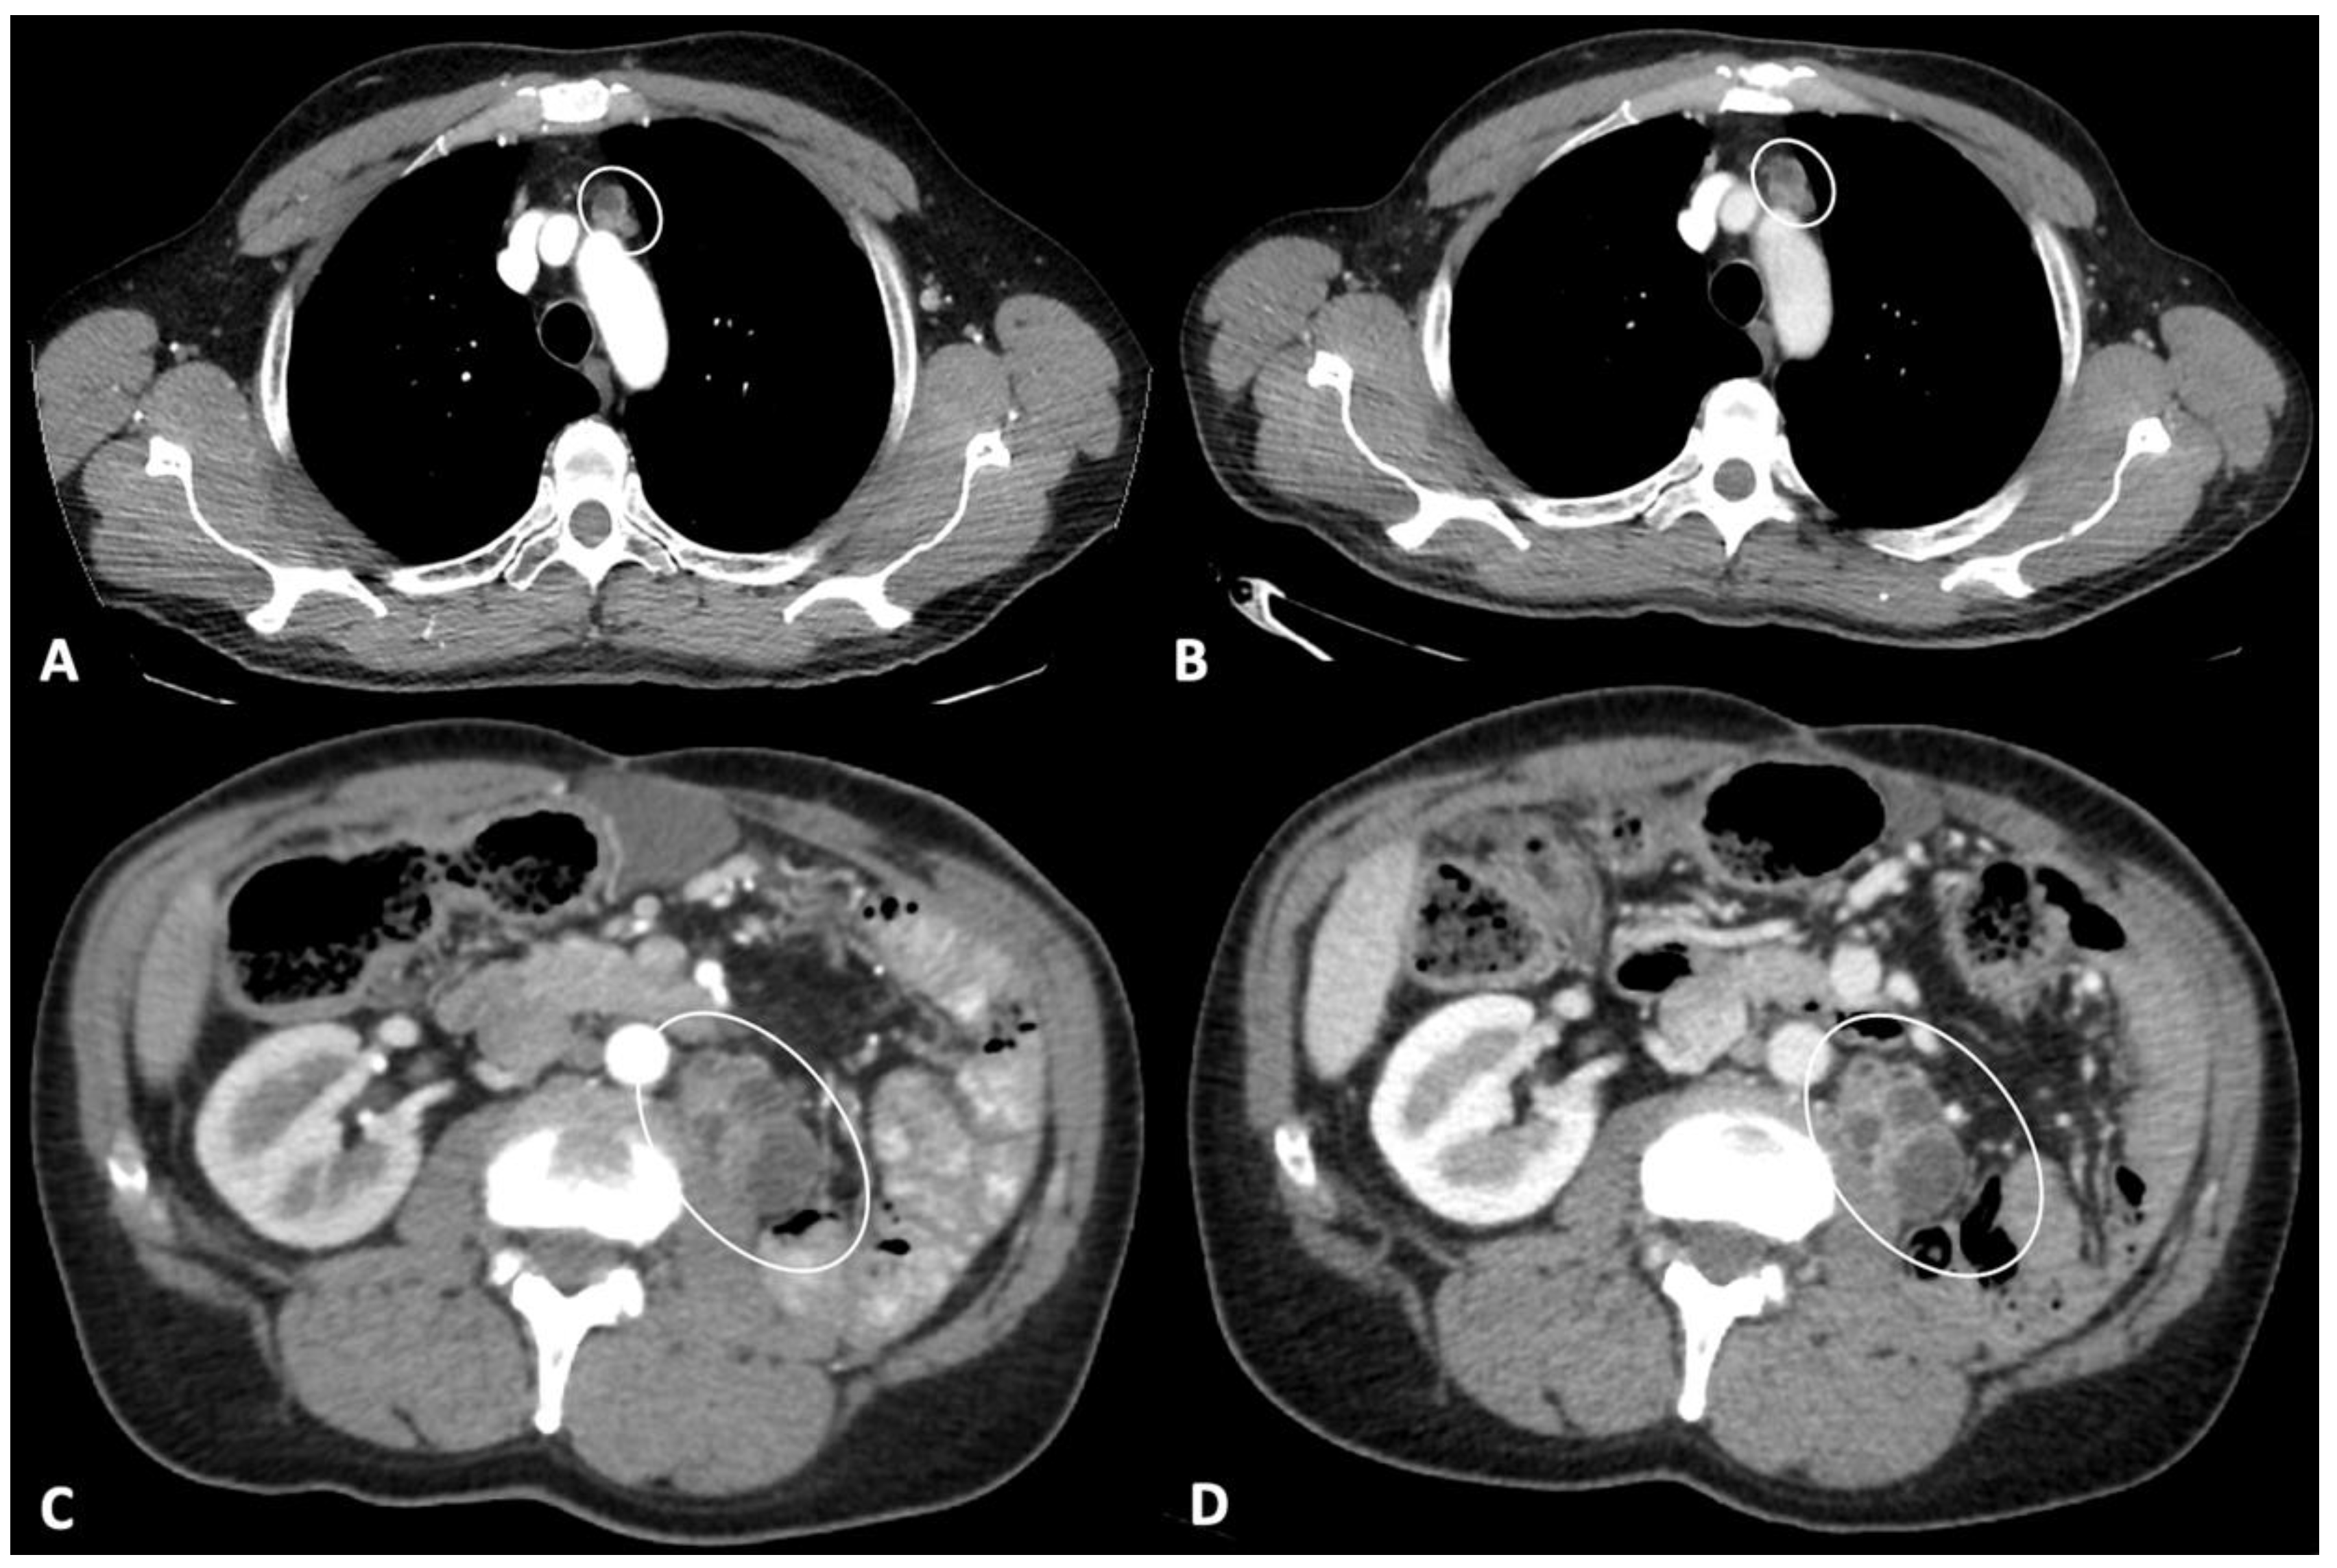

- Smith, A.D.; Lieber, M.L.; Shah, S.N. Assessing tumor response and detecting recurrence in metastatic renal cell carcinoma on targeted therapy: Importance of size and attenuation on contrast-enhanced CT. Am. J. Roentgenol. 2010, 194, 157–165. [Google Scholar] [CrossRef] [Green Version]

- Thian, Y.; Gutzeit, A.; Koh, D.-M.; Fisher, R.; Lote, H.; Larkin, J.; Sohaib, A. Revised choi imaging criteria correlate with clinical outcomes in patients with metastatic renal cell carcinoma treated with sunitinib. Radiology 2014, 273, 452–461. [Google Scholar] [CrossRef] [PubMed]